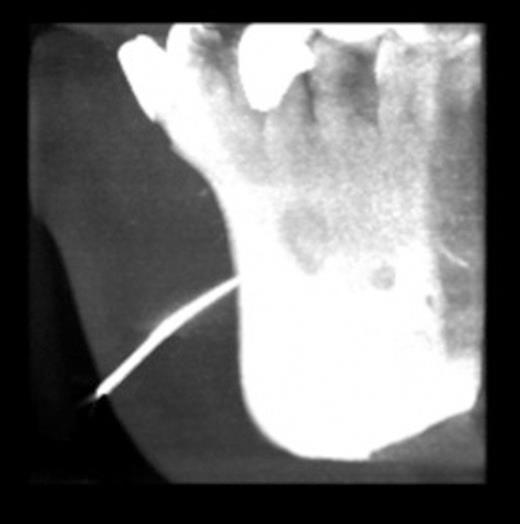

Plain radiographs revealed a periapical radiolucency of the lower left first premolar. A gutta percha (GP) point was inserted into the sinus. Cone beam computed tomography (CBCT) showed the GP point to be in communication with the periapical area (Fig. 3 & 4).

CT showing gutta percha point communicating with the periapical area